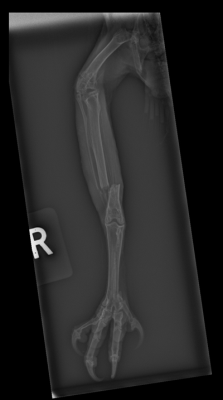

Our multi-disciplinary team of specialists anaesthetised and radiographed the owl, with orthogonal views of the right tibia revealing a mid-diaphyseal, displaced, complete transverse fracture. Fracture repair using external fixation was planned, and undertaken, by consultant orthopaedic surgeon Dr David Sajik.

The right limb was plucked and following aseptic preparation, a mini medial approach to the tibia was utilised to expose the fracture site. The fracture was successfully reduced and maintained in position whilst two, 1.1mm threaded pins, were placed in the proximal and distal fracture fragments. The ends of the pins were bent over and incorporated into an epoxy putty ‘free-form’ connecting bar. Routine closure of the surgical site was performed using 3-0 Monocryl intradermal sutures. Post-operative radiographs confirmed perfect fracture reduction with appropriate implant positioning and the owl recovered uneventfully from anaesthesia.